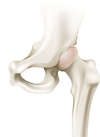

Comment fonctionne l’articulation de la hanche ?

L’articulation de la hanche appelée aussi articulation coxo-fémorale met en relation la cavité articulaire du bassin (Cotyle) et la tête fémorale. Ces deux structures sont fermement emboîtées et sont entourées d’une capsule articulaire, de puissants ligaments et d’une chape musculaire. La mobilité de la tête fémorale dans le cotyle est facilité par le cartilage qui recouvre les deux surfaces osseuses et par le liquide articulaire ou synovial qui améliore le mouvement et nourrit le cartilage.

Elle possède une mobilité dans les trois plans de l’espace : d’avant en arrière (flexion/extension), latéralement (abduction/adduction), et en rotation (interne/externe). Elle est animée par des muscles parmi les plus puissants de l’organisme tels que les muscles fessiers.